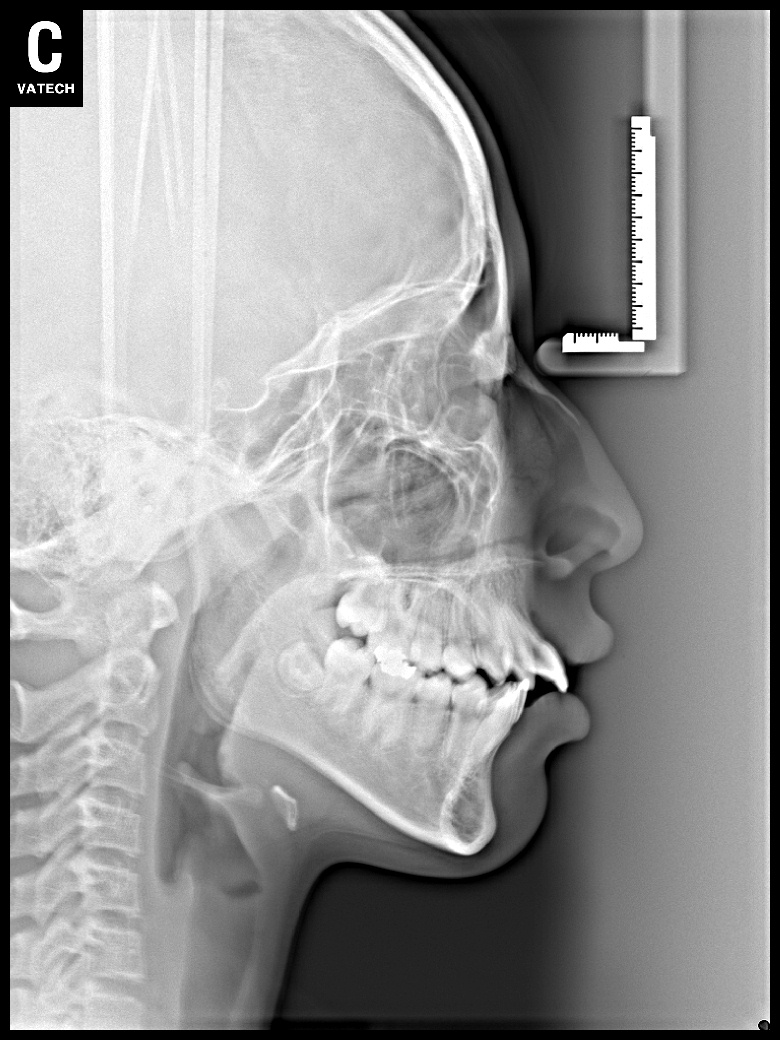

치료 전 사진입니다.